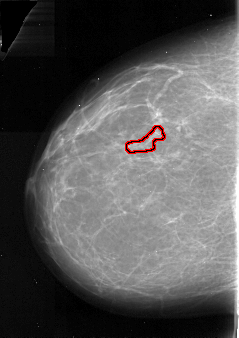

A_1083_1.RIGHT_CC

RIGHT_CC LINES 5326 PIXELS_PER_LINE 3421 BITS_PER_PIXEL 16 RESOLUTION 42 NON_OVERLAY

FILE: A_1083_1.LEFT_CC.OVERLAY

TOTAL_ABNORMALITIES 1

ABNORMALITY 1

LESION_TYPE CALCIFICATION TYPE PLEOMORPHIC DISTRIBUTION LINEAR

ASSESSMENT 4

SUBTLETY 2

PATHOLOGY MALIGNANT

TOTAL_OUTLINES 1

BOUNDARY